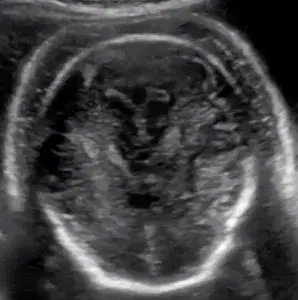

Explore case studies on fetal hydrops, focusing on its causes, echocardiographic findings, and clinical management. This course provides valuable insights for healthcare professionals to enhance their understanding of this complex condition and improve prenatal diagnostic and care strategies.

Understand the ultrasound definitions of non-immune hydrops and its possible etiologies.

Develop a systematic approach to aid in determining the diagnosis when non-immune hydrops is suspected.